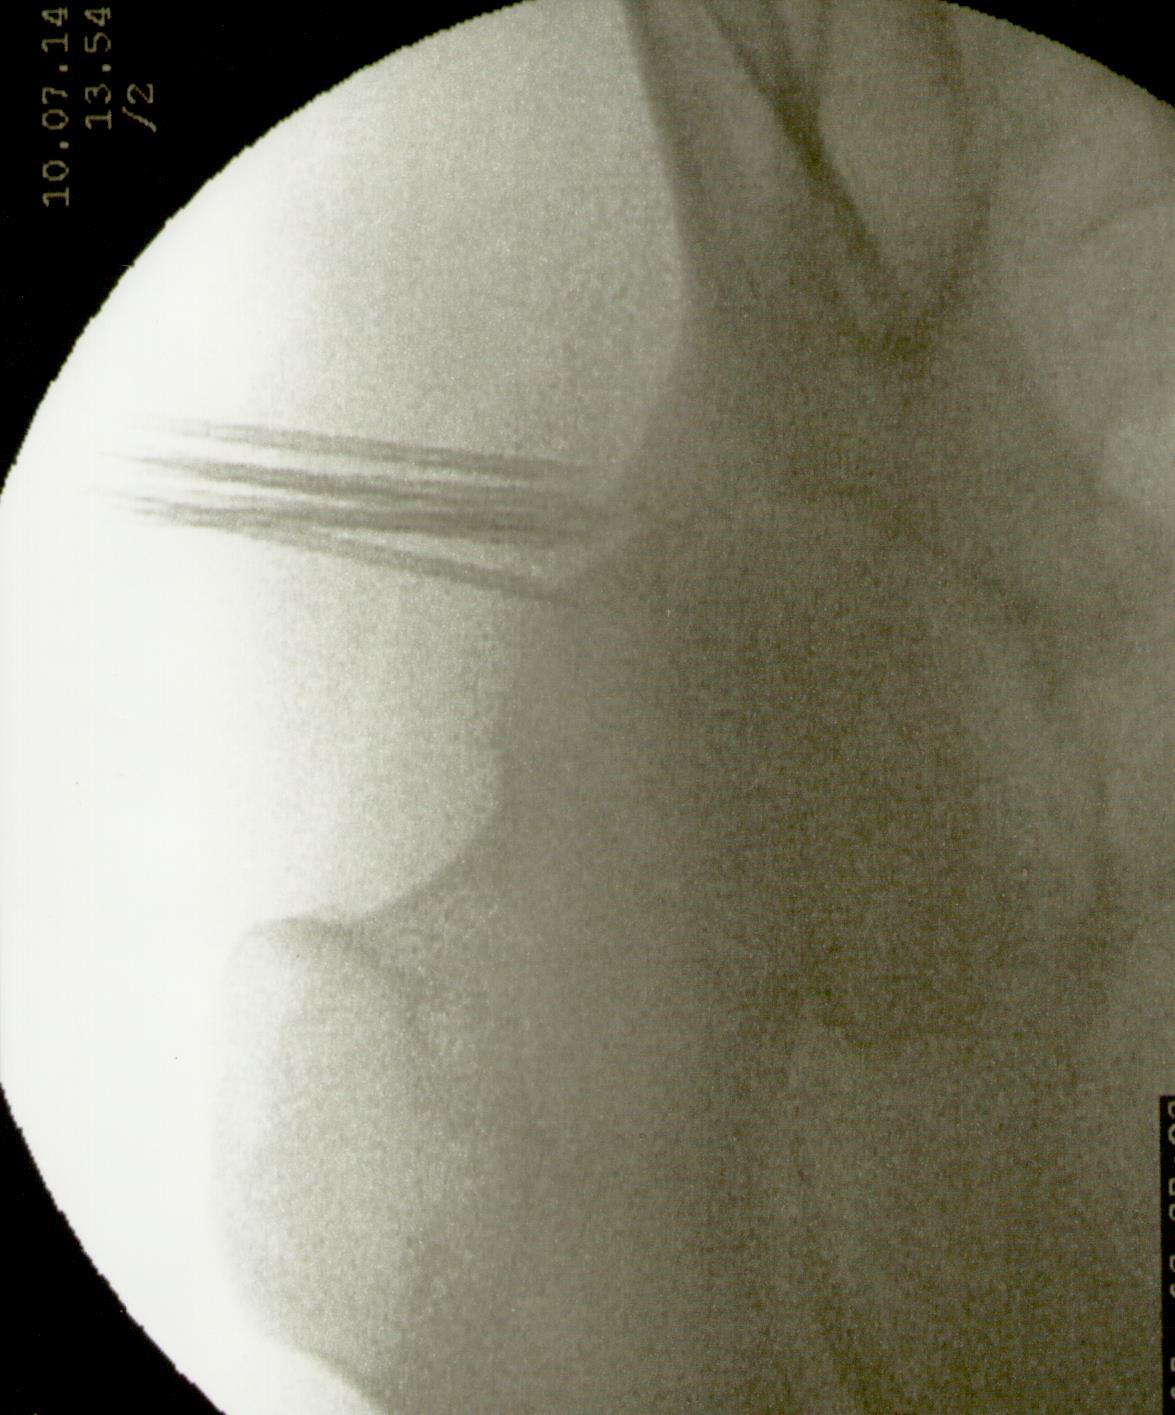

Más abajo se observarán unas imágenes de casos de implantes de oro en cadera